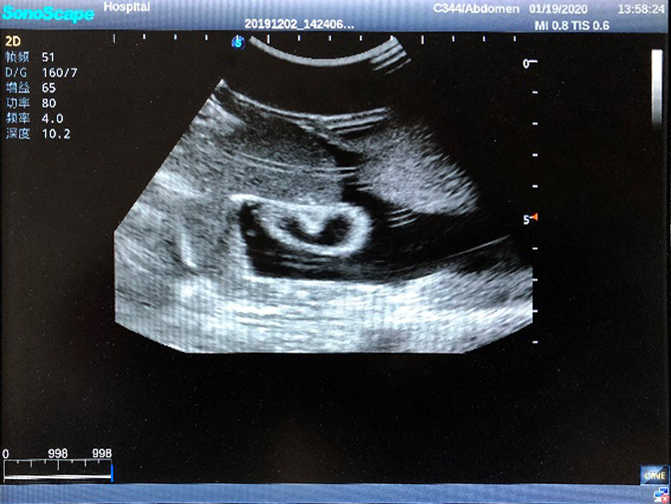

2)  High quality ultrasound image with clear structures like gallbladder, liver, intestines, arteries and veins etc.

3)  Compatible with all types of clinical ultrasound machines